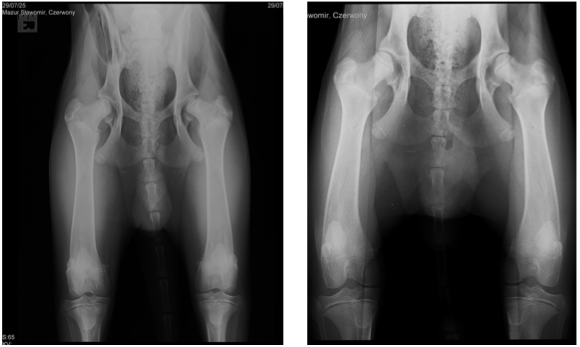

Dysplazje stawów biodrowych

Dysplazje stawów biodrowych polegają na nieprawidłowym dopasowaniu głowy kości udowej do panewki stawu biodrowego. Prowadzi to do niestabilności stawu oraz stopniowego uszkadzania chrząstki stawowej, a co za tym idzie, powstawania zwyrodnień i powstawania biodra płaskiego (coxa plana).

Diagnostyka dysplazji

Rozpoznanie dysplazji opiera się na badaniu ortopedycznym oraz diagnostyce obrazowej. Najczęściej stosowane badania to:

- badanie kliniczne i ortopedyczne,

- badanie rentgenowskie (RTG),

- tomografia komputerowa (TK),

- artroskopia diagnostyczna.

Badania te pozwalają ocenić stopień zmian oraz zaplanować odpowiednie leczenie.